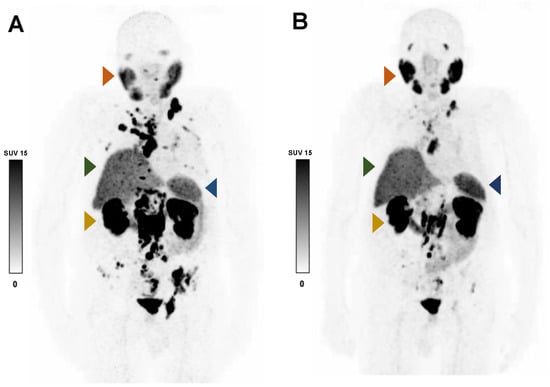

Figure 4.

Representative 68Ga-PSMA-11 PET MIP images of an 86-year-old patient with advanced mCRPC who responded to RLT before (A) and after (B) two cycles of 177Lu-PSMA-617. After decreases in TLP (−83%) and serum PSA (−92%), the SUVmean increased in the right parotid gland (ΔSUVmean +32.9%; orange arrow) and the spleen (ΔSUVmean +21.2%; blue arrow), but it was minimally changed in the liver (ΔSUVmean +7.0%; green arrow) and right kidney (ΔSUVmean +0.6%; yellow arrow).